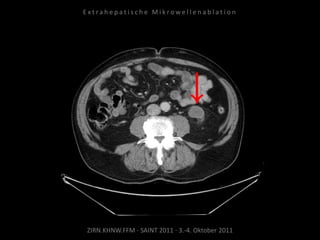

Patient: Weiblich, 66 Jahre

Diagnose: Ovarial-Ca,

progrediente retroperitoneale

Lymphome, u.a. am Truncus coeliacus

und der Arteria mesenterica superior.

Zunehmende Drucksymptomatik im

Oberbauch.

Bildgebung vor MWA:

CT 09.09.2010

Situation:

Tumorerkrankung mit ausgedehnter

Metastasierung. Schmerzsymptomatik

durch Metastasen am Truncus coeliacus.

Ziel:

Druckreduzierung durch Reduzierung

der Tumorlast, thermische Reduktion

der Schmerzfasern am Truncus, dadurch

Reduzierung der hierdurch bedingten

Beschwerden. Kein kurativer Ansatz.

Indikation zur MWA:

Aufgrund der gefäßnahen Lage stellt die

MWA mit ihrer der exakten

Positionierbarkeit und dem exakt

definierten Ablationsvolumen die

Methode der Wahl dar.

Ablation am 07.10.2010:

Je eine Nadelposition von links und

von rechts.

Kontrolle:

CT 08.10.2010

CT 05.11.2010

Kein Progress im abladierten Areal.

Erfolgreiche Schmerztherapie.

CT 03.12.2010

CT 03.05.2011

Resultat:

Kein weiteres Tumorwachstum im

abladierten Areal. Schmerzsymptomatik

deutlich gebessert.

Fazit:

Die MWA ist außerhalb eines kurativen

Ansatzes geeignet, Tumorwachstum zu

bremsen und Symptomatik zu

vermindern.